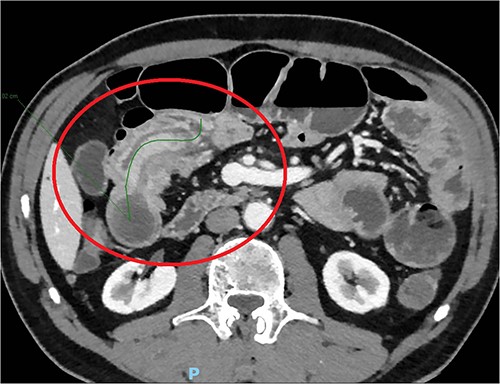

The day after, the new abdominal X-ray documented increasing distension of the bowel, with multiple hydro-aerial levels and it was decided to perform an abdominal CT scan with iodinated contrast agent: this revealed an ileo-ileal invagination extending in the mesogastrium region for about 10 cm, without showing the characteristics of expansive neoformations (Fig. 1).